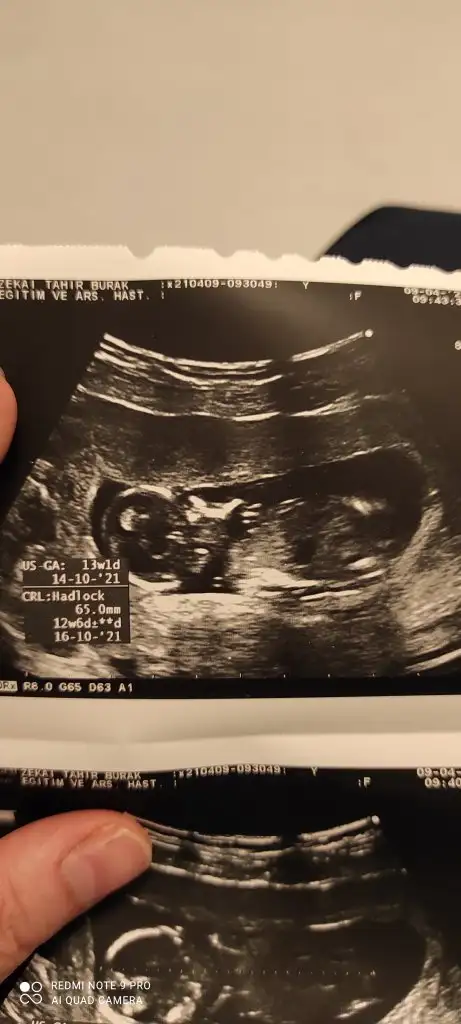

Ikra meyra Ikra meyra 12+1 sata göre bana da bakar mısınız çok hareketli oldugu için bişey demedi Dr

• IMG_20210409_103243.webp

IMG_20210409_103243.webp

41,4 KB · Görüntüleme: 65

• IMG_20210409_103239.webp

IMG_20210409_103239.webp

30,5 KB · Görüntüleme: 78